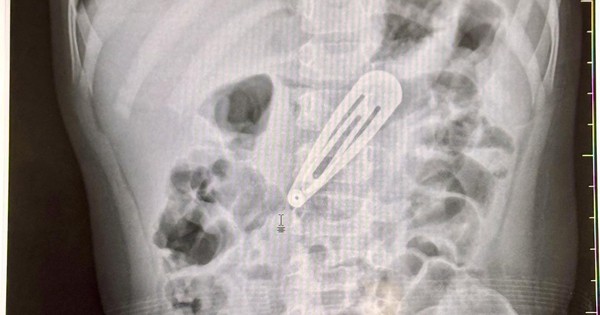

Hình ảnh chiếc kẹp tóc trong dạ dày bệnh nhi. Ảnh: BVCC.

Sau khi thăm khám lâm sàng và chụp X-quang bụng, các bác sĩ ghi nhận hình ảnh một dị vật kim loại nằm trong ổ bụng, tương ứng vị trí dạ dày của bé. Bệnh nhi nhanh chóng được chuyển sang Trung tâm Nội soi tiêu hóa và Thăm dò chức năng để tiến hành nội soi can thiệp lấy dị vật ra ngoài.

BSCKI Tô Duy Thư cho biết: Dị vật là chiếc kẹp tóc kim loại, dẹt, đầu tù, cạnh sắc, nằm ở vùng thân vị (phần giữa của dạ dày). Mặc dù dị vật không quá nhọn, nhưng cạnh sắc và kích thước lớn dễ gây thủng rách trên đường di chuyển, đặc biệt khi di chuyển xuống ruột non – vị trí lòng ruột nhỏ, thành mỏng – có thể gây rách, thủng hoặc tắc ruột cơ học. Khi dị vật gây thủng ruột hay gây tắc ruột (thời gian dài có thể dẫn tới hoại tử đoạn ruột), nếu không tiến hành phẫu thuật kịp thời có thể dẫn đến nguy cơ tử vong.

May mắn, chiếc kẹp tóc trong trường hợp này chưa gây tổn thương đến niêm mạc tiêu hóa. Qua nội soi, các bác sĩ ghi nhận dị vật vẫn nằm trong dạ dày, chưa gây rách hay thủng. Dị vật được cố định bằng dụng cụ chuyên dụng và gắp ra thành công, không để lại biến chứng. Sau thủ thuật, sức khỏe bé ổn định.